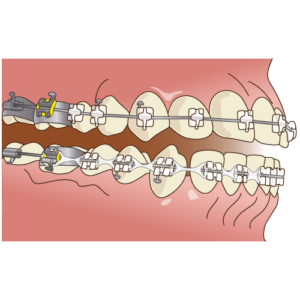

歯の表面に装置(ブラケット)を接着し、そこにワイヤーを通すことで歯を移動させていきます。

②装置を装着してスタート